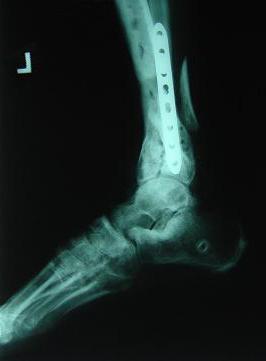

Post-corrective surgery X-Rays of the damaged right & left legs / ankles

The first two x-rays show Liam’s left ankle and pelvis prior to the accident. For comparison purposes it is interesting to see the

differences. The next x-rays were taken after the corrective surgery performed by Dr. Armendariz. Noticed that Dr. Armendariz has used tibia

bracing and also aligned the bone fragments of the left leg so that they could heal in the proper orientation. The external fixation has been

removed and Liam’s left foot has been returned to a more natural alignment.